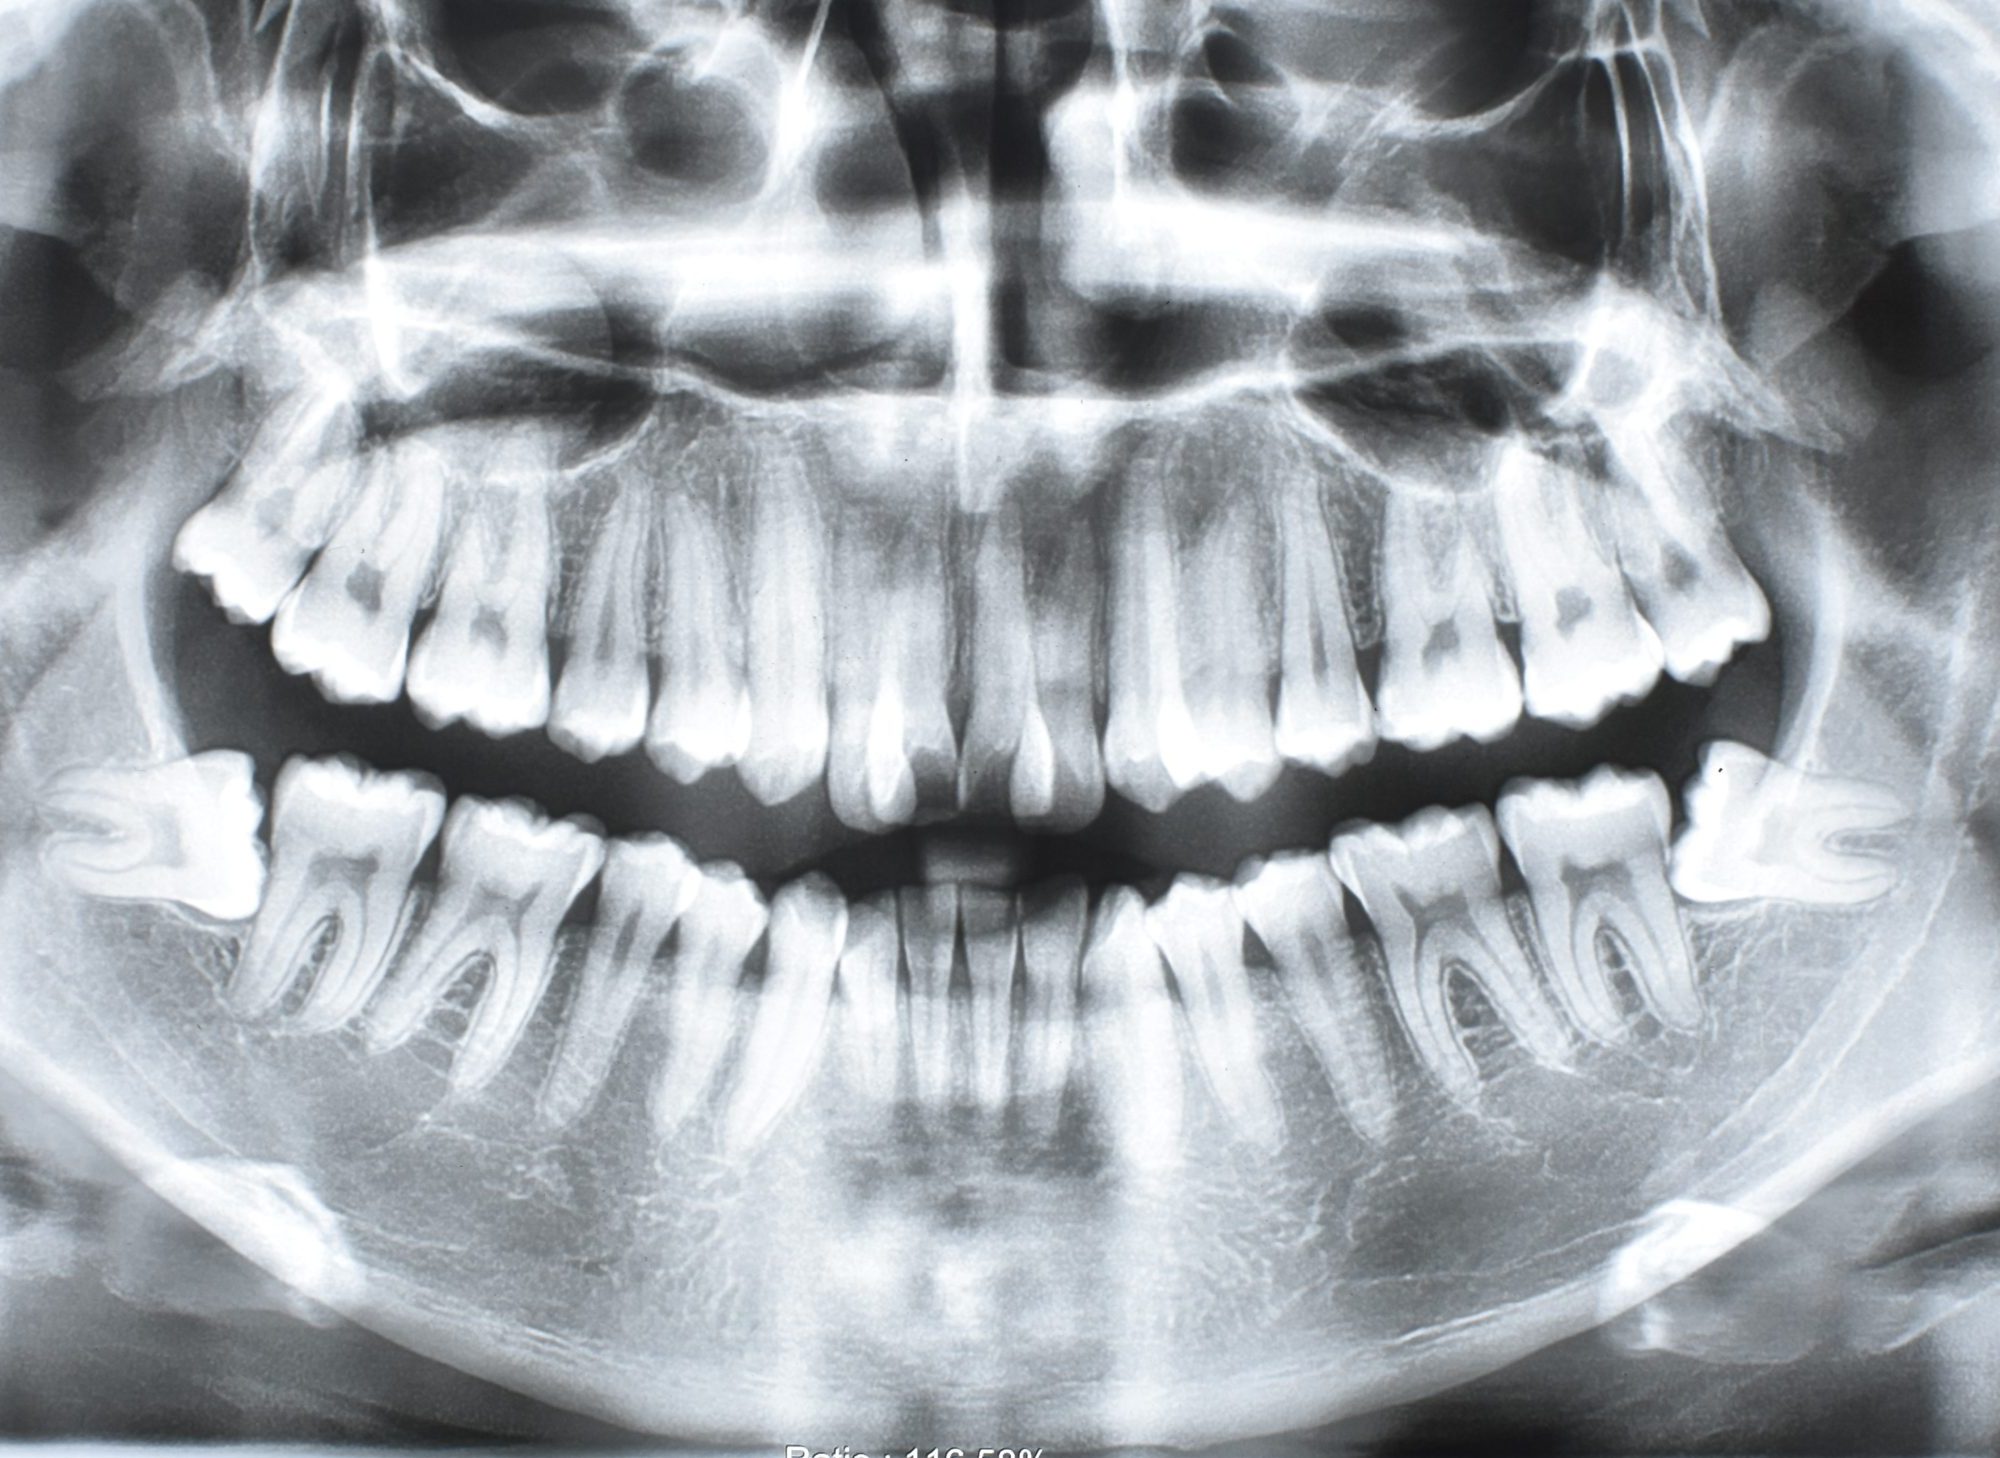

Canino retenido / Maxilar sin desarrollo completo

Paciente de 18 años con canino retenido (entre paladar y piso de fosas nasales) y maxilar sin desarrollo completo.

Se hace valoración Ortodontica con tomografía, para hacer cirugía de sutura palatina. Esta se descarta y se realiza disyunción con Orto implantes.